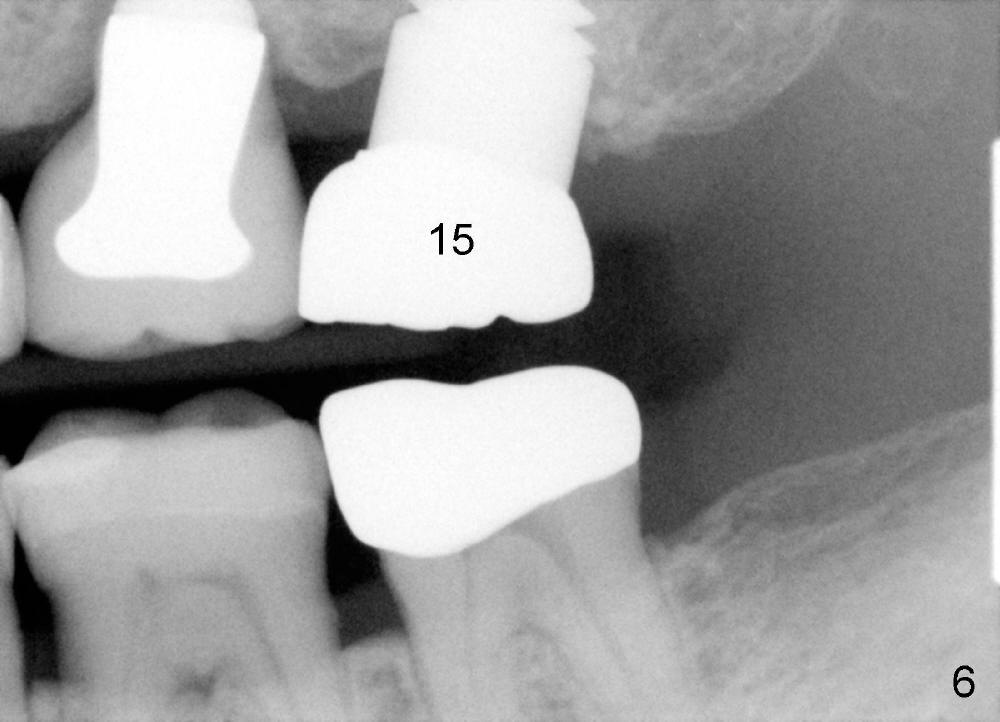

A 71-year-old male is a bruxer. His upper left fixed partial denture was lost 4 years ago (Fig.2). It is replaced by an implant (Fig.3: #14) and two single unit crowns (#13,15). One year later, the tooth #5 is replaced by an immediate implant due to crown fracture (Fig.1,4). Six months after the cementation of #5 implant crown, the tooth #15 is restored by an immediate implant due to root fracture (Fig.6). Recently, porcelain chips off the PFM crown of #13. The patient finally agrees to have another implant (Fig.1: #2) to make his dentition complete and distribute masticatory force more evenly.

The advantage to place implants for a bruxer is that there is sufficient bone height (Fig.2-4). The bone density also appears to be high; there is a thick cortical bone in the edentulous ridge of #2 (Fig.4 arrowheads). Incision will be made; suture may be required for flap fixation. Osteotomy is initiated by 2 mm pilot drill 4 mm from the neighboring tooth (Fig.5); the depth is 8 mm. The depth of the osteotomy is adjusted according to X-ray taken with a parallel pin. Sinus lift may be needed (Fig.5 dashed line: sinus floor). The density of the cancellous bone will be felt and determined while using the 2 mm pilot drill for initial osteotomy. If the density is high, Bicon reamers will be used for further osteotomy and bone saving. Otherwise, osteotomy will be finished mainly with Bone Expander Kit or osteotomes. Bone-level implant is used, followed by a healing abutment. Decortication will be done with a surgical handpiece with a fissure or round bur. If no suture is used for flap fixation, perio glue will be used to close the incision without perio dressing. If the wound is not approximated each other well with sutures, perio glue can be used for complete seal.

Further search of the patient's files finds X-ray taken prior to #5 extraction (Fig.7). Bone height is estimated 12 mm. Since the mesiodistal width of the 1st molar is less than 10 mm (Fig.8), the center of the osteotomy at the site of #2 should be 4.5 mm (3.5 mm from the 2 mm pilot drill). If the bone allows, 5.3x12 implant will be placed.